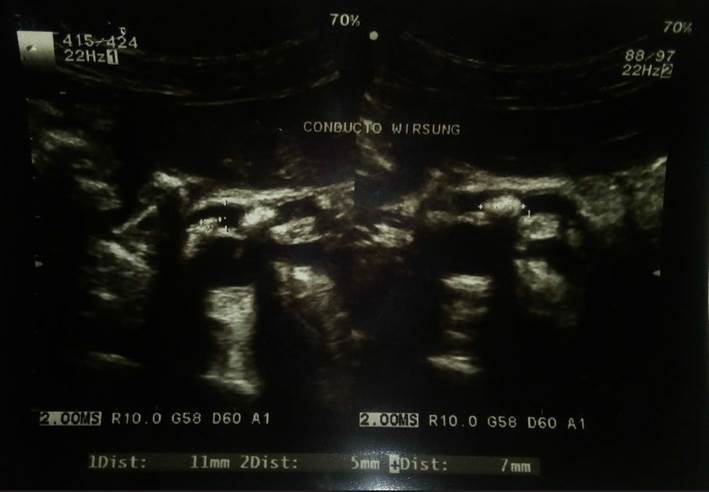

En el examen presenta un regular estado general. Ventila espontáneamente, sin dificultad. Tiene una SatO₂:95 %, PA: 80/60 mmHg y las demás funciones vitales eran estables. Peso = 44 kg, talla = 1,58 m, IMC = 17,6 kg/ m2, pálida (+/+++), moderado pasaje del murmullo vesicular sin ruidos agregados y dolor a la palpación profunda en epigastrio e hipocondrio derecho. En el resto de la evaluación no muestra nada particular. Se solicitan exámenes auxiliares y se inicia tratamiento con escopolamina e hidratación con NaCl 0,9 %. Exámenes auxiliares: glicemia= 670 mg/dL; creatinina = 0, 94 mg/dL; urea= 24 mg/dL; hemograma= 13 320 leucocitos/ uL (Ab:4 %, Seg:73%, Eo:2 %, Mon:1 %, Linf:20 %); Hb=10,3 g/dL; Hto = 32,3%; plaquetas = 684 000/uL; examen de orina (+); Gram s/c= bacilos gramnegativos, 90-95 leucocitos/campo, 8-10 hematíes/campo, trazas de glucosa, nitritos (++/+++). AGA y electrolitos: pH =7,348; pCO₂=39,3 mmHg; HCO₃-= 21,8 mmol/L; Na+ = 123,1 mmol/L; K+ = 3,26 mmol/L; Cl- = 89,2 mmol/L; Ca++ = 0,65 mmol/L; Mg++ = 0,23 mmol/L. Inician el tratamiento con insulina R 10 UI stat y luego a escala. También solicitan un urocultivo e inician la antibioticoterapia. Se indica realizar controles glicémicos en horario y la paciente se hospitaliza. La antibioticoterapia continúa hasta que en el urocultivo aparece una bacteria nosocomial y varía la sensibilidad antibiótica, entonces el tratamiento cambia a imipenen y la evolución continúa de manera favorable. Se inicia terapia con insulina NPH 22 UI/día, la cual se aumenta hasta un máximo de 52 UI/día en un periodo de 15 días; sin embargo, no se logró un adecuado control y la paciente continúa con picos de hiperglicemia y, en algunas oportunidades, seguidos de hipoglicemias de hasta 36 mg/ dL, por lo que se decide cambiar la insulina NPH por insulina glargina, la cual se inicia con 10 UI/día y se aumenta hasta 32 UI/día. Después, se añade insulina tipo aspart 5 UI con el almuerzo y 5 UI con la cena, con lo que se logra un mejor control. Se le solicitó una ecografía (Figura 1), la que muestra litiasis múltiple en el conducto de Wirsung que está dilatado, por lo que se solicita una colangioresonancia que confirma la litiasis en el conducto de Wirsung y su dilatación, así como atrofia pancreática difusa severa, con lo que se diagnostica la pancreatitis crónica. La paciente es dada de alta luego de 30 días de hospitalización con la remisión del cuadro infeccioso, un mejor control glicémico con insulina glargina 26 UI/día, insulina tipo aspart 5 UI con el almuerzo y 5 UI con la cena, y el tratamiento enzimático, así como con indicaciones de control por gastroenterología.

Figura 1 Estudio ecográfico que evidencia el conducto de Wirsung dilatado (7 mm), en cuyo interior se observan múltiples imágenes litiásicas, la mayor de 11mm